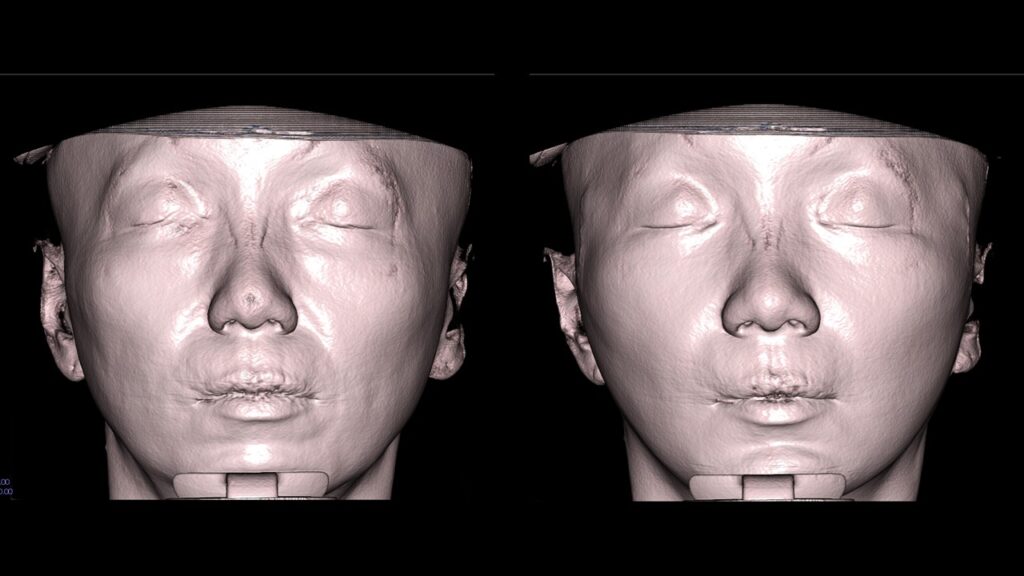

4. Case Studies (3DCT & Medical Photos)

Case 1: (Zygoma Reduction + Face Lift) 1-year post-op shows a significant reduction in mid-face width and improvement in nasolabial folds.

Case 2: (Zygoma + Chin Advancement + Face Lift + Brow Lift) Dramatic improvement in the side profile and double chin within just 1 month.